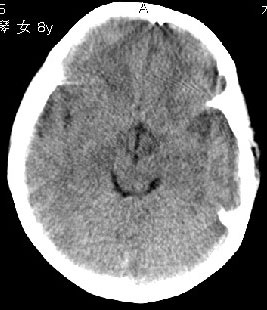

杨某,女,8y,家长述2006.10.13行破伤风疫苗注射后下肢疼痛,后自行粘贴膏药未见好转

,后续发现左上肢肢力下降。于2006.10.28在我院行ct检查,发现右侧基底节区片状低密度影,

无占位效应。ct值约:18~20hu。边界清晰,与相邻脑室无通连。未行增强扫描。余脑实质

未见异常。

右侧内囊后支、丘脑见片状低密度区,边界不清,无占位效应。

从ct图像看,准确地说病变是在右侧丘脑,累积右侧内囊后肢。

因为图像差一些,不能完全排除大脑半球其它区域有无病灶。如果大脑半球其它区域有病灶,则支持脑炎的诊断。有条件应该尽早进行mr检查。